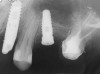

A 55-year-old male was referred for implant placement and prosthetic rehabilitation in the area of tooth No. 15. The tooth had been extracted 4 years prior. The radiograph revealed inadequate bone height for implant positioning (Figure 6). It was decided to insert an implant that was 11.5 mm in length and 3.75 mm in diameter, performing a slight osteotomic maxillary sinus lift. A heterologous bone graft also was planned to obtain a larger sinus lift.

Figure 6 Preoperative radiograph of the area around tooth No. 15.